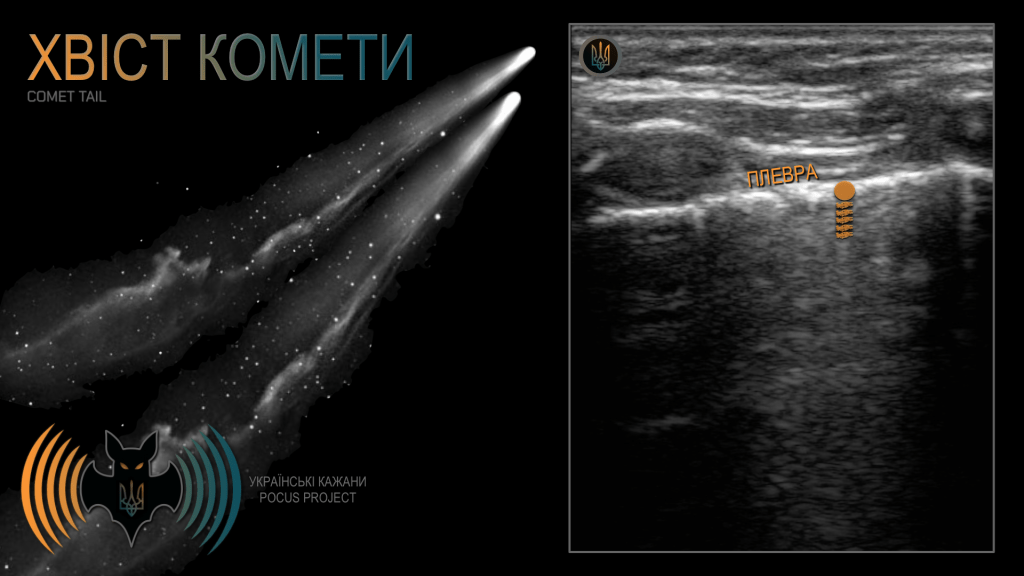

ХВІСТ КОМЕТИ: це ревербераційний артефакт, який виглядає як короткий, яскравий «хвіст» ехо-сигналів, що відходить від високо відбивної межі. Він виникає тоді, коли УЗ-промінь «захоплюється» між двома щільно розташованими поверхнями та багаторазово між ними відбивається. З кожною реверберацією імпульс, що повертається до датчика, стає значно слабшим і швидко згасає. Найчастіше цей артефакт спостерігається при ковзанні плеври (як у нашому прикладі) або на кінчику голки у доступі out-of-plane (коротка вісь).